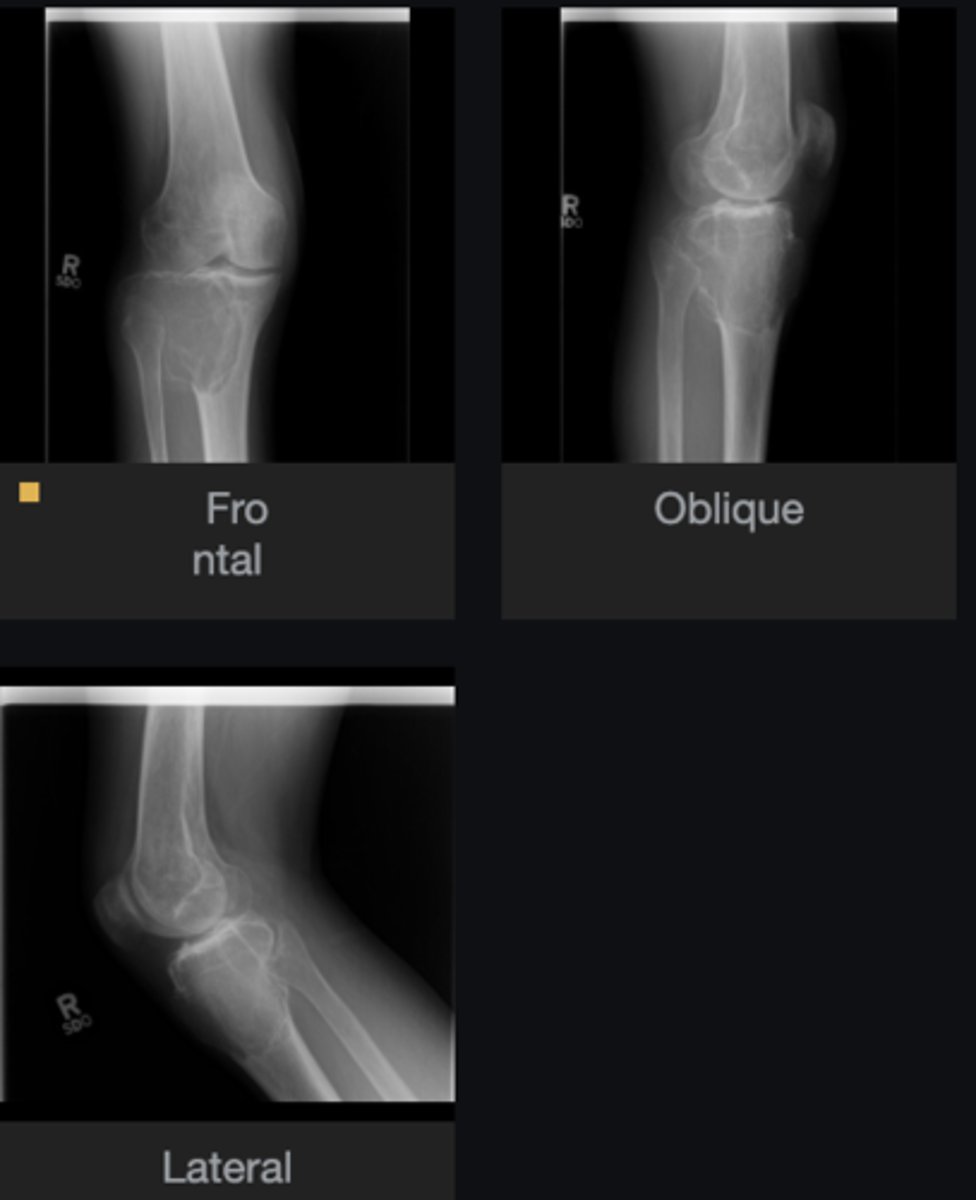

- Ulna

- Diaphysis

- Sclerotic

- Small, lucent nidus (< 1cm) in the cortex

- Geographic)

- Cortical thickening

Describe the lesion

Osteoid osteoma

Most likely diagnosis?

Severe pain (worse at night, relieved by aspirin)

What is the hallmark history of a patient with this lesion?

- Refer to orthopedist

- Adjust spine

Next step?

None

Concerns/complications?